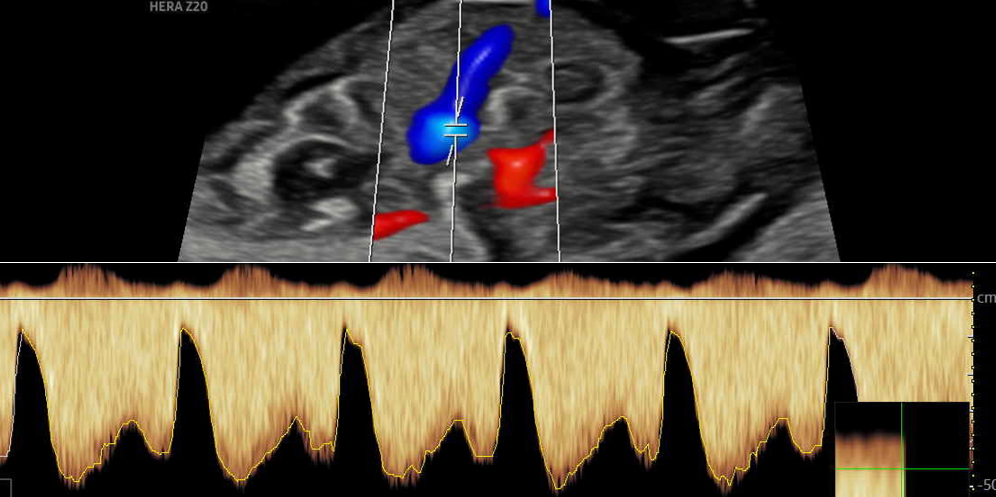

Doppler

Bei dieser Untersuchung messen wir die Durchblutung in der Nabelschnur und anderen Blutgefäßen, um die Versorgung Ihres Kindes zuverlässig einzuschätzen und zu überwachen. Je nach Fragestellung ist diese Untersuchung ab 11 SSW möglich.